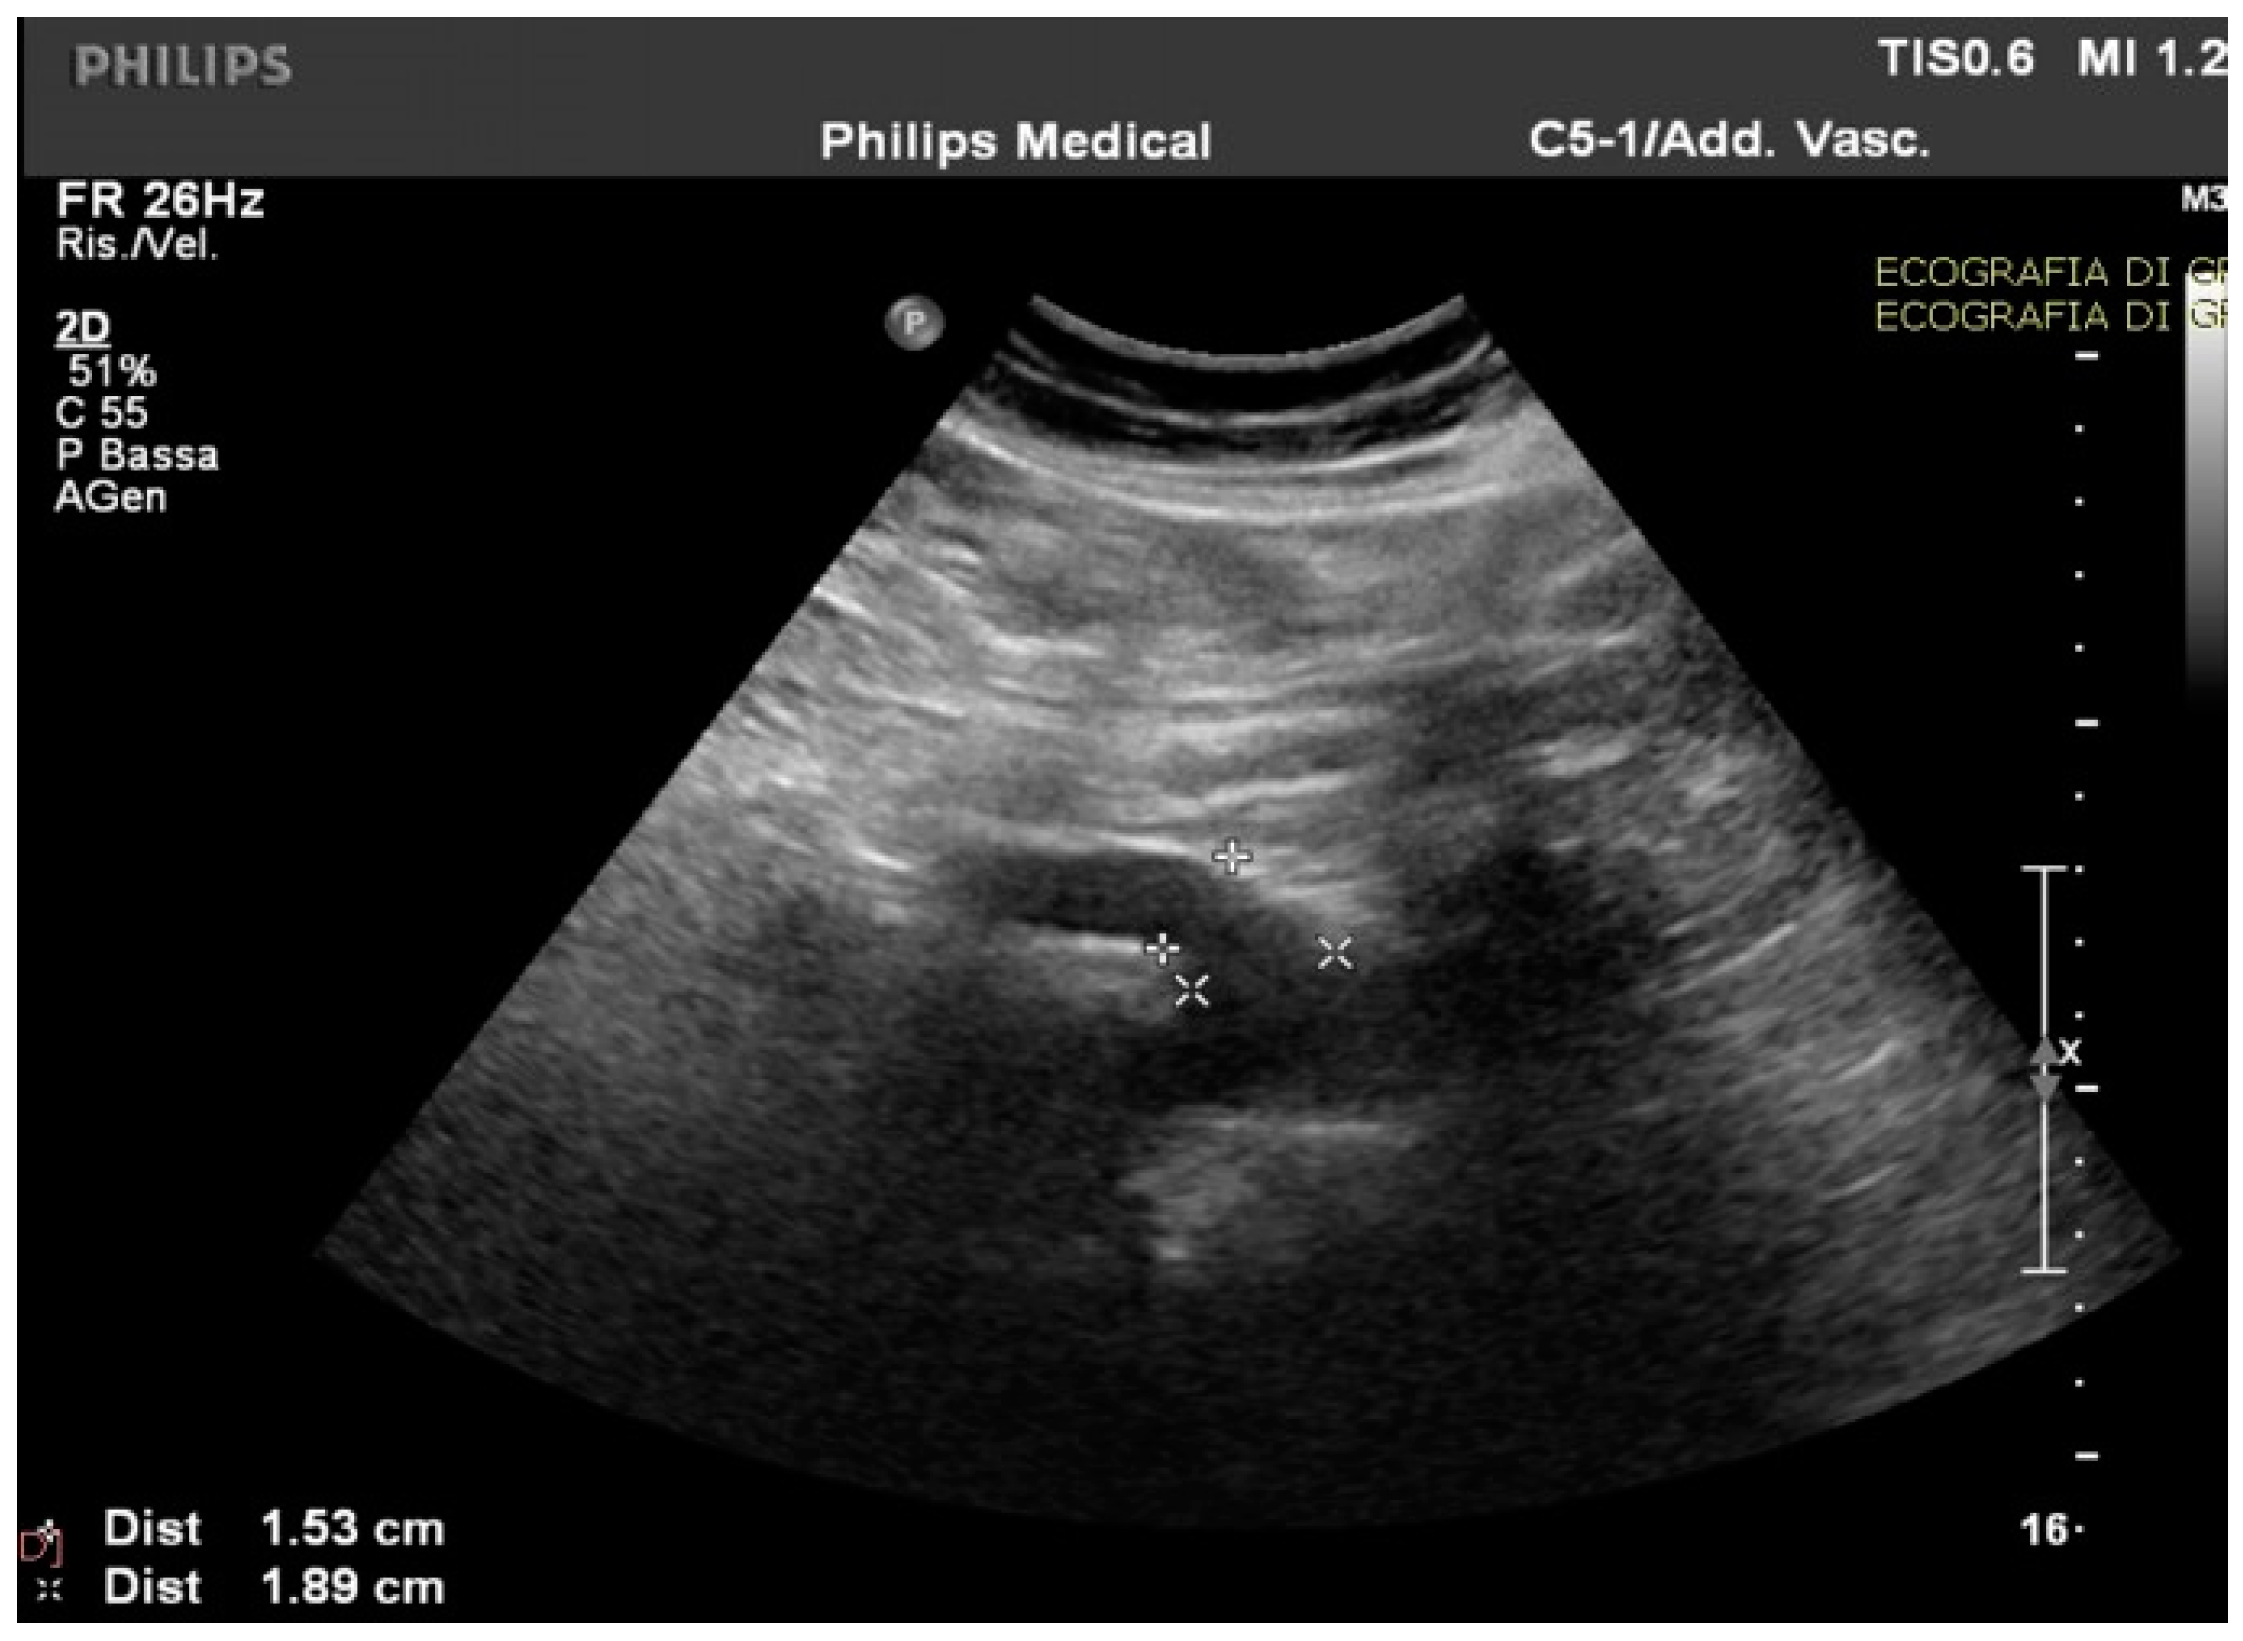

Routine and specific blood and stool tests (according to the diseases’ epidemiology in our region, Sardinia, Italy) for hepatic, pancreatic, intestinal, infectious, celiac, autoimmune, and hematological diseases showed normal results. The upper endoscopy and colonoscopy were negative for significant findings. Interestingly, in the ultrasound scan of the abdomen cavity, we noticed agenesis of the left hepatic lobe, splenomegaly, and enlargement (1.89 cm at the ostium and 1.53 cm downstream) of the CMT (normally ranging between 0.7 to 1 cm) (Figure 1).

Figure 1.

The celiac-mesenteric trunk observed by an ultrasound scan of the abdomen, indicating the size of the proximal and distal site.

Abnormalities were also present in the CT scan with and without contrast medium (Figure 2 and Figure 3).

Figure 2.

The computer tomography scan confirmed the agenesis of the left hepatic lobe, splenomegaly, and an enlarged celiac-mesenteric trunk (red arrow).